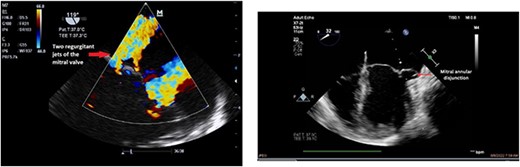

Clinically, both patients complained of worsening palpitations over the last few months with no associated dyspnea or tiredness. A Holter examination recorded 14 444 VES and 212 NSVT, with very similar results in both sisters. The echocardiography revealed a myxomatous Barlow mitral valve with anterior and posterior leaflet prolapse and two regurgitant jets resulting in moderate to severe mitral valve regurgitation as well as mitral annular disjunction in both cases (Figs 1 and 2). A cardiac MRI on a 3 T Lumina Siemens revealed at the mid-left ventricular level, a midwall fibrosis in the midlateral myocardium (Figs 3 and 4) and confirmed a mitral annular disjunction of 12 mm (Figs 5 and 6). Additional findings included a dilated LV with mildly depressed contractility, no visible myocardial scarring, no structural heart disease and a normal sized RV with mildly depressed contractility.

Both sisters underwent a minimally invasive procedure through a right-sided lateral minithoracotomy performed at the level of the third or fourth intercostal spaces. Cardiopulmonary bypass was established through a femoral access and cardioplegic cardiac arrest was achieved through a modified Del Nido solution (20 ml/kg). Mitral valve repair was performed through isolated annuloplasty using in both cases a 38-mm semi-rigid annuloplasty ring. Transesophageal echocardiography after repair revealed excellent surgical results, with no rest regurgitation, no SAM of the mitral valve and most importantly no detectable mitral annular disjunction (Figs 7 and 8). In both cases, being performed several months apart, the patients were extubated in the operating room and transferred to our ICU for further observation.